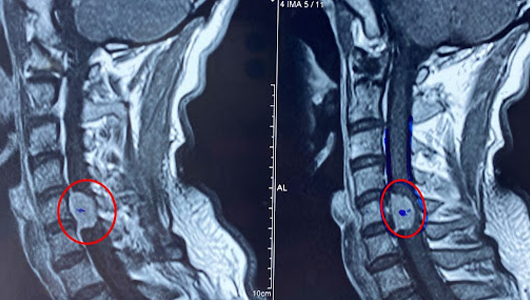

4. Cận lâm sàng chèn ép tủy sống.

4.5. Cộng hưởng từ hạt nhân:

5.2. Chẩn đoán vị trí: